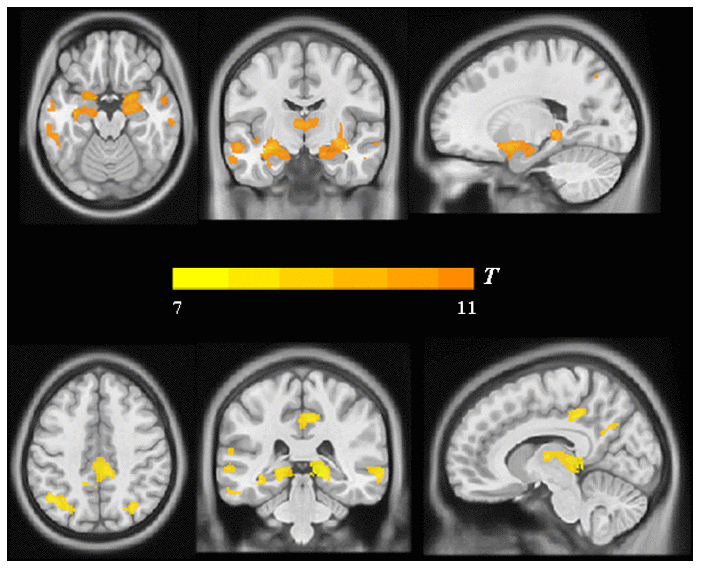

Moreover, the findings described above were further confirmed by whole-brain confirmatory analysis. Relative to the NC group, the results of the AD group were also replicated and showed significantly reduced GM volume in bilateral hippocampus, right amygdala, the PCC and the bilateral angular gyrus (P < 0.001, FWE-corrected, Figure 3 and Table 2), as well as significantly reduced metabolism in multiple regions including the PCC and bilateral angular gyrus within the DMN (Figure 4 and Table 2), which was still significant after regressing out the whole-brain GM volume (Figure 5 and Table 2).

Figure 3. Group differences in VBM analysis between the AD group and the NC group. Significant reduced gray matter volume in AD patients was shown in warm yellows.